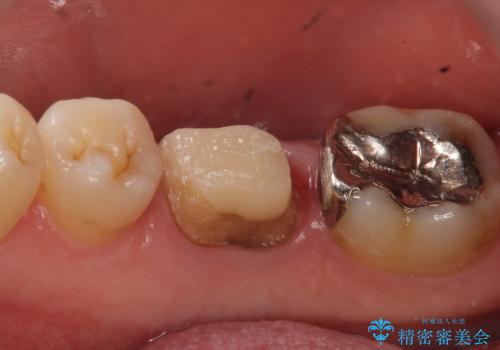

- 数年前から歯茎から膿が出る、治療してもよくならないので診て欲しいといらっしゃった方の症例です。

再根管治療を行い膿の出口の消失及び根尖病変の縮小を確認後、オールセラミッククラウンによる補綴を行いました。